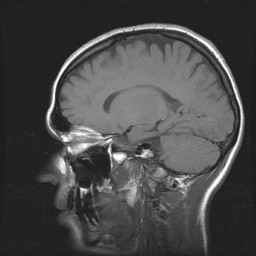

Schedel